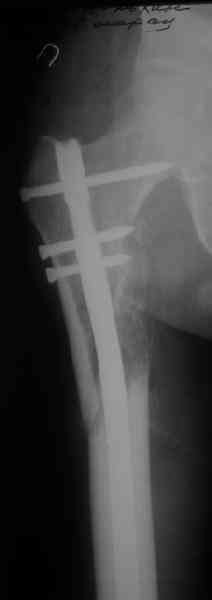

Вот несколько. С тисками и трубой на днях сделаем.

> Вот несколько. С тисками и трубой на днях сделаем.

Саша, последний штифт, пожалуй, перегнули?

> Саша, последний штифт, пожалуй перегнули?

Там заход сделан как для прямого штифта, не через вертел.